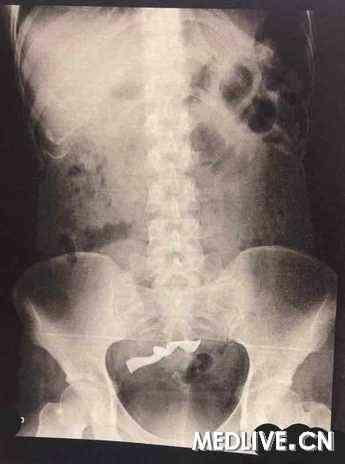

1. 胆囊结石:这是最常见的病因。胆囊结石会导致胆囊发炎,严重时甚至可能引发胆囊癌。为了防止病情恶化,医生会建议切除胆囊。